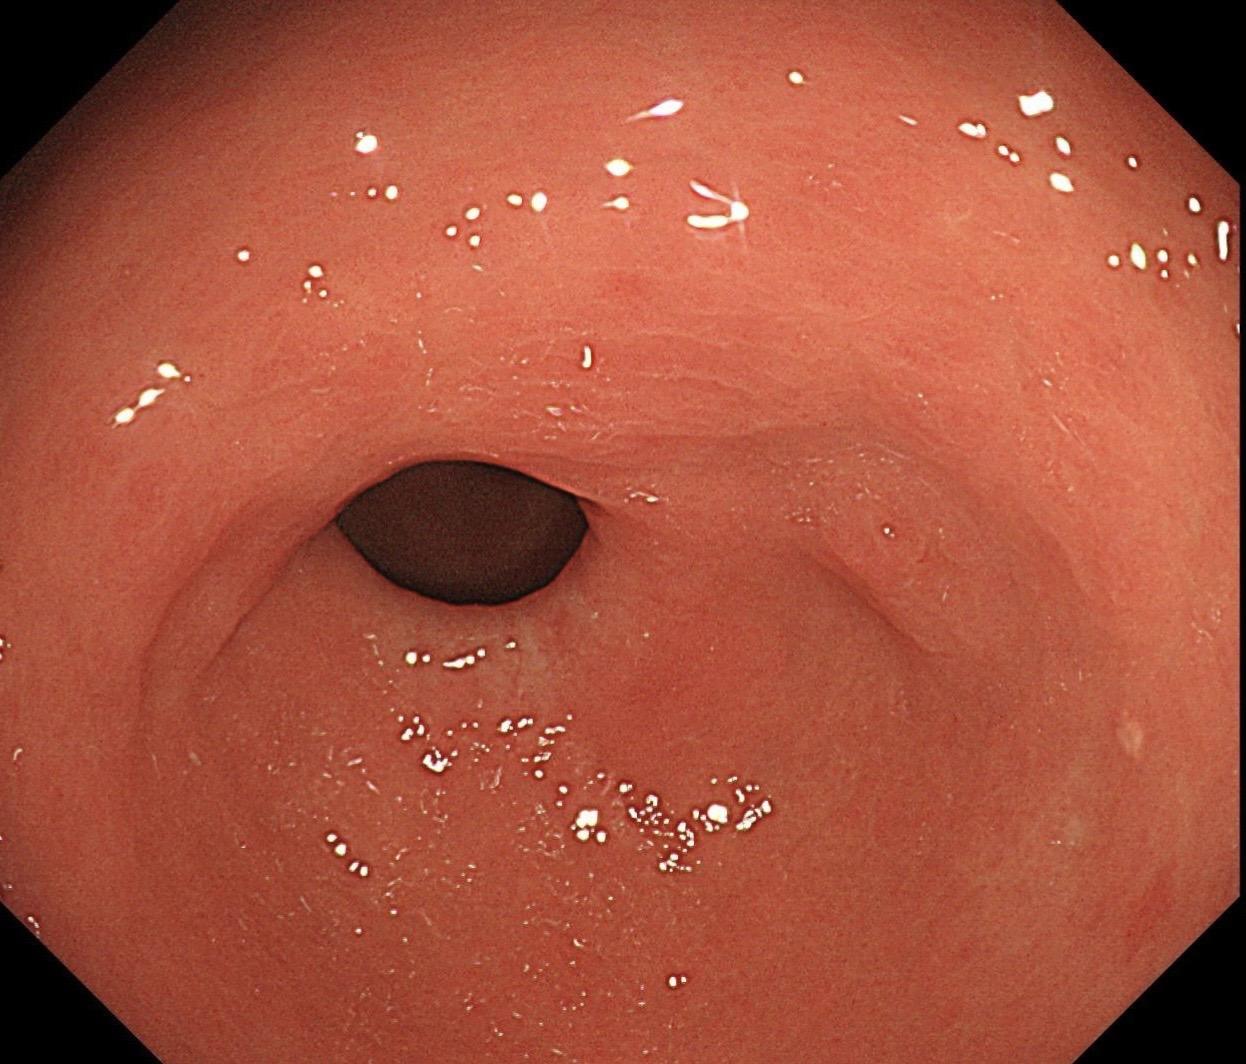

萎缩背景,注意那些微小的发黄色调。